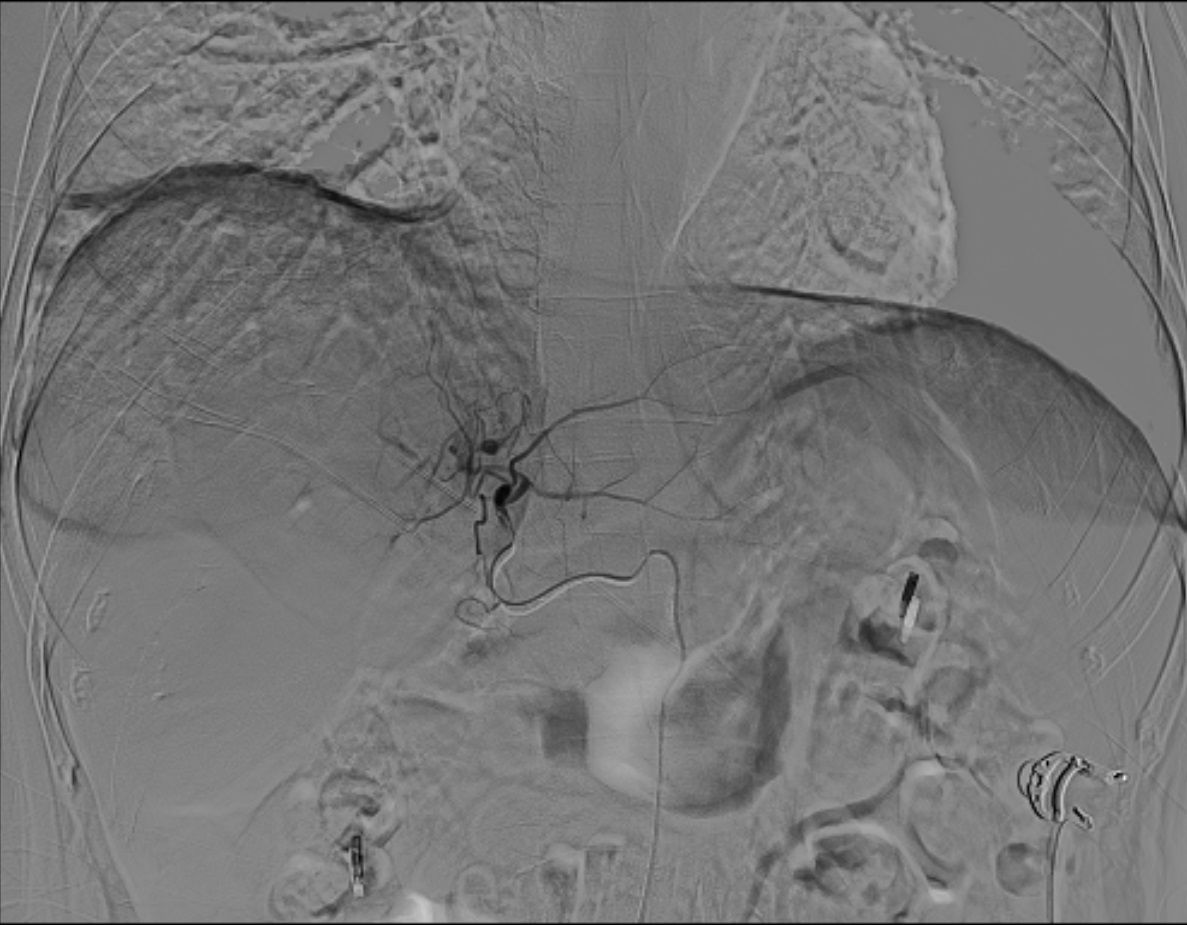

3.3 Enhanced tumor feeder arteries identification with dual CBCT

As illustrated in Figure 4 and Figure 5, conventional 2D angiography often present overlapping normal hepatic arterial branches and tumor-feeding arteries, making their distinction challenging. In contrast, dual CBCT enabled rapid and accurate identification of tumor-feeding arteries, enhancing the precision of 90Y therapy delivery. This technology successfully identified tumor-feeding arteries in all 27 cases, achieving a 100% success rate.

Figure 4

Angiographic imaging of the human abdomen, showing the vascular structures with contrast highlighting the blood vessels. The aorta and major branches are visible in a grayscale format, providing detailed insights into the vascular anatomy and any potential abnormalities.

Figure 4. Conventional 2D angiography shows overlapping normal hepatic arterial branches and tumor-feeding arteries, making distinction challenging.